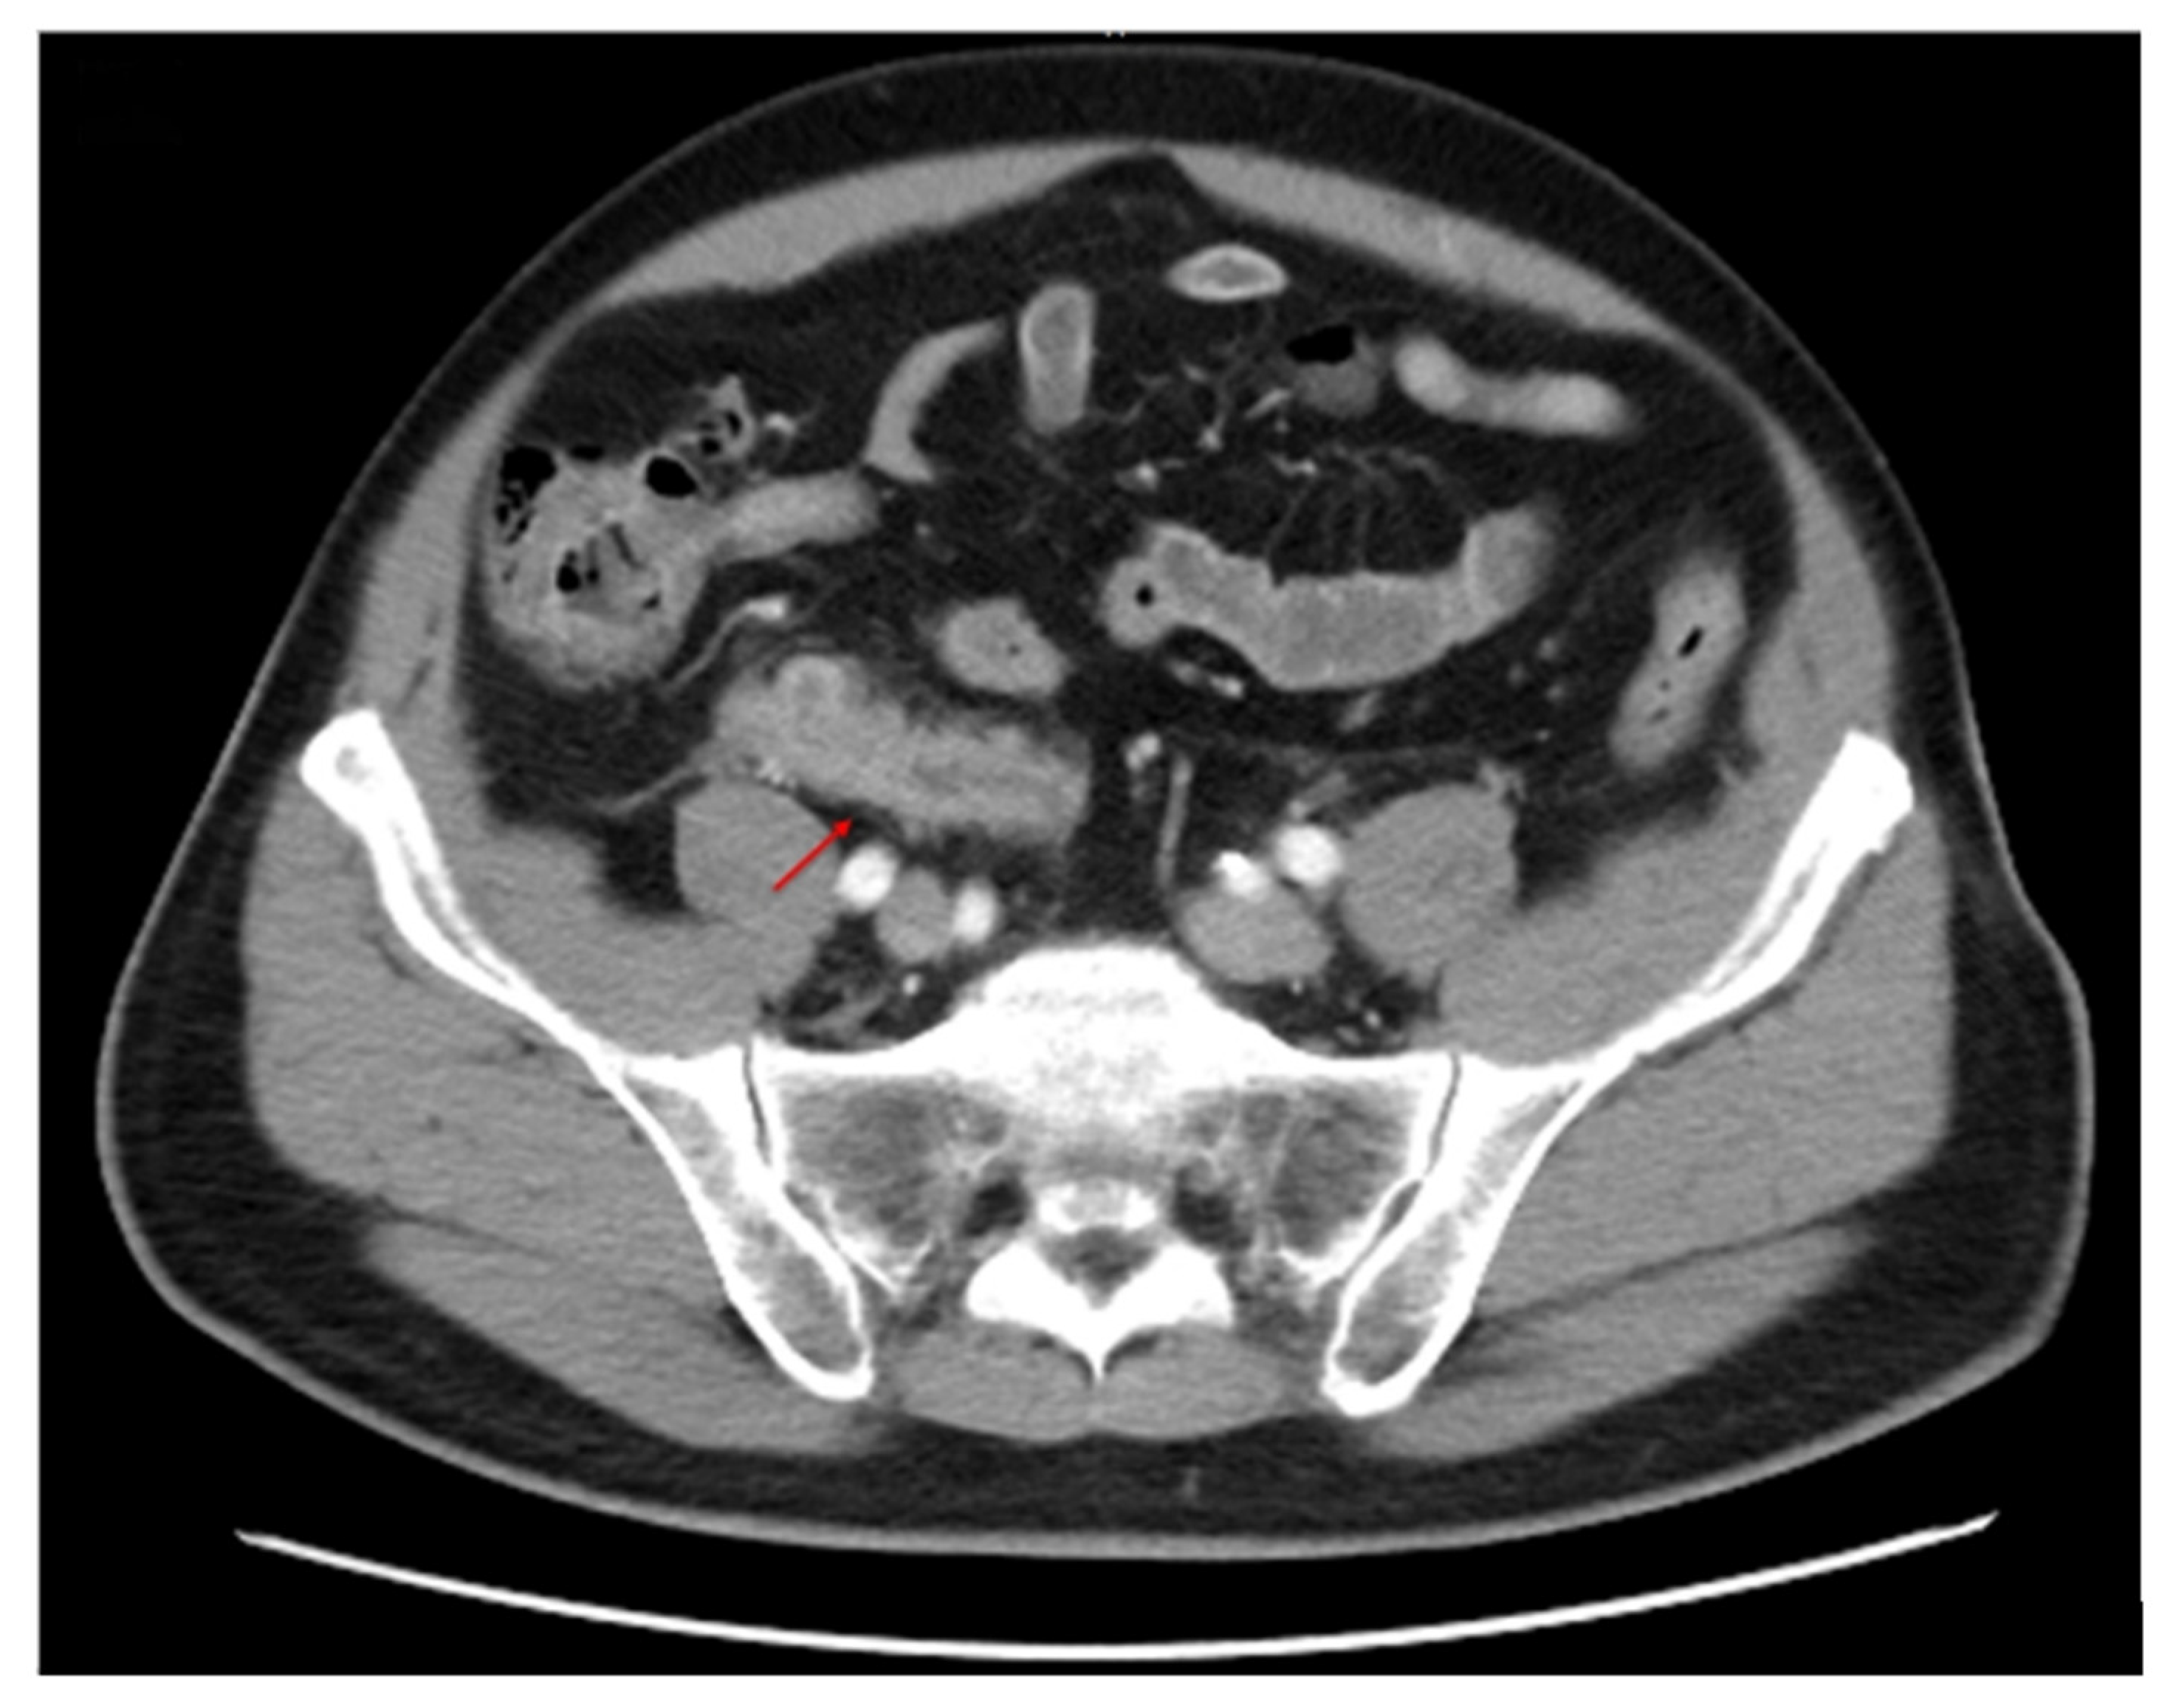

| Linden et al. [12] | 71/M | Mantle cell lymphoma | Appendectomy | CD3(+), CD5(+), CD20(+), Cyclin D1(+) Bcl-6(−), Ki-67:60–80% | Right-sided abdominal after starting 1st cycle of chemotherapy. Abdomen CT revealed enlarged appendix with perforation. | 6 months |

| Gaopande et al. [13] | 50/F | Acute calculous cholecystitis | Cholecystectomy Appendectomy | CD20(+), cyclin D1(+), CD3(−), CD10(−) | Right upper abdomen pain Abdomen CT revealed tumor over right iliac fossa | 3 years |